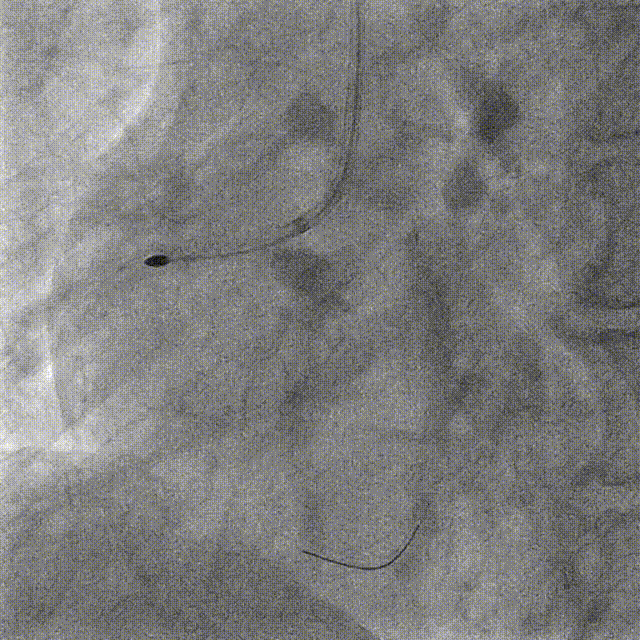

Lesion preparation NC 2.5*12mm → Cutting balloon 4.0*10mm @ 12atm

Angiography & DCB Angioplasty DCB 4.0*20mm @ 8atm, 60s

ROTA with 2.0mm burr

Angiography & Angioplasty NC 2.5*12mm